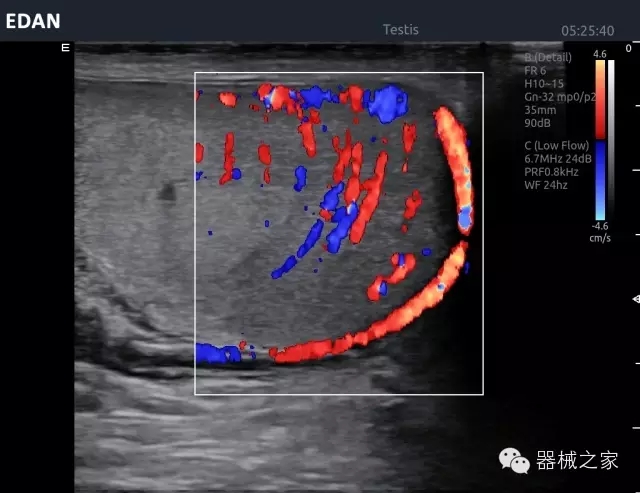

品牌:理邦儀器(EDAN)

經(jīng)典產(chǎn)品:Acclarix AX8

臨床圖片賞析

睪丸低速血流